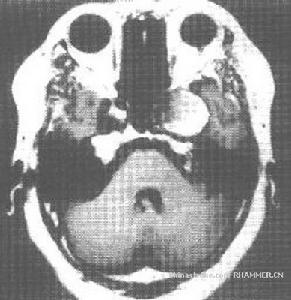

(1)小腦半球症狀:主要表現為患側肢體共濟失調,還可出現患側肌張力減弱或無張力,膝腱反射遲鈍,眼球水平震顫,有時也可出現垂直或鏇轉性震顫。

(2)小腦蚓部症狀:主要表現為軀幹性和下肢遠端的共濟失調,行走時兩足分離過遠,步態蹣跚,或左右搖晃如醉漢。

(3)腦幹症狀:特徵的臨床表現為出現交叉性麻痹,如中腦病變多,表現為病變側動眼神經麻痹,橋腦病變,可表現為病變側眼球外展及面肌麻痹,同側面部感覺障礙以及聽覺障礙,延髓病變可出現同側舌肌麻痹、咽喉麻痹、舌後1/3味覺消失等。

5、小腦橋腦角症狀:常表現為耳鳴,聽力下降,眩暈,顏面麻木,面肌抽搐,面肌麻痹以及聲音嘶啞,食水嗆咳,病側共濟失調及水平震眼。